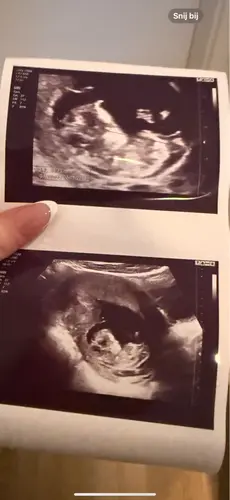

Eerlijk gezegd, kan ik bij alle onderstaande foto’s niets uithalen.. ze zijn te wazig, nub niet goed zichtbaar

Net geslachtsbepaling gehad en het is inderdaad een jongen!

Gefeliciteerd 🩵 wat weet je vroeg het geslacht met 12 weken? Ik dacht dat dit pas kon bij 14+ weken. 🙈